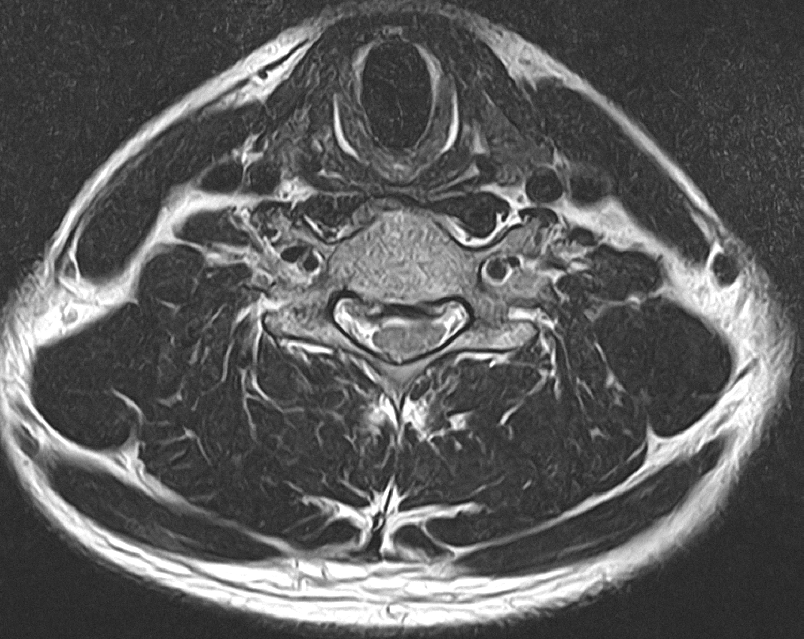

• 3번 째 사진

해당 단면이 척추의 어느 부위인지를 알 수 있으면 더 정확한 판단이 가능합니다.